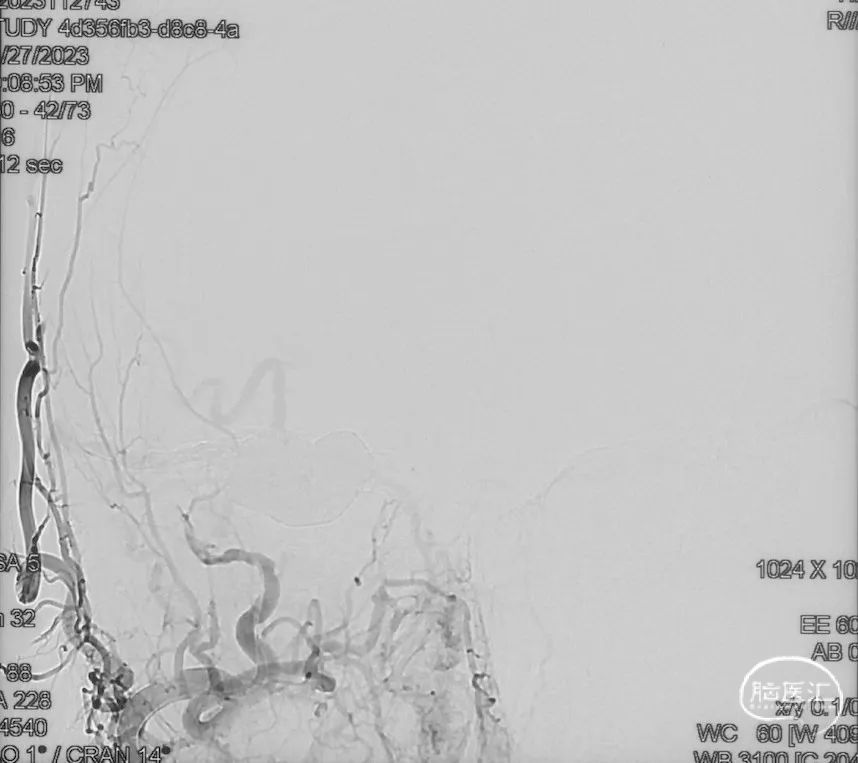

Echelon-10微导管在ASAHI 0.010微导丝导引下经右侧脑膜中动脉分支超选至瘘口,可见瘘口口径大,微导管直接越过瘘口,进入引流静脉起始部。

Marathon微导管在ASAHI 0.010微导丝导引下经右侧脑膜中动脉分支超选至瘘口近端。

经Marathon微导管手推造影明确微导管位于瘘口动脉端,Echelon-10微导管位于瘘口引流静脉起始端处扩张的静脉球内。

由于瘘口流量大,为了防止栓塞材料过度弥散,并逃逸至深静脉,首先通过Echelon-10微导管向静脉球内填入Feng 12/40、Feng 10/30两枚弹簧圈,限制后续液态栓塞材料仅在静脉起始部弥散。

随后回撤Echelon-10微导管,并通过Echelon-10微导管和Marathon微导管交替注入Onyx-34、Onyx-18,此时可见Onyx首先被血流冲至静脉球内,但被弹簧圈篮筐限制,并在瘘口范围内弥散。

通过“注射-停顿-再注射”,Onyx进一步在瘘口及供血动脉段和引流静脉起始部弥散满意

造影显示瘘口不显影,无静脉早显。